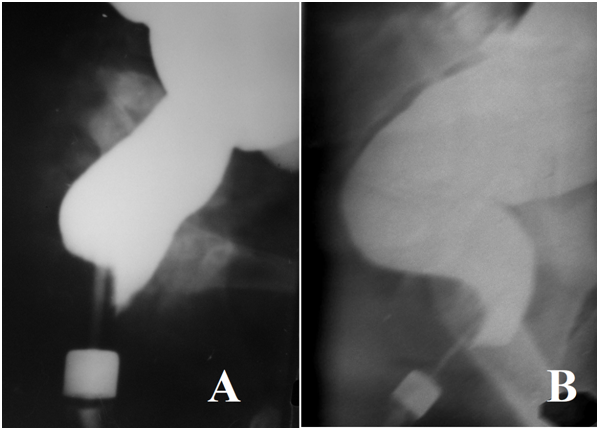

In children older than 3 years, the loop of the sigmoid colon is always located in the pelvis. The dome of the cecum in infants has a symmetric semi-oval shape. In older age groups, sometimes a deformation of the dome appears. In infants, the appendix was filled with barium in 89% of cases, but in other age groups, only in 39% of cases. Haustration of the colon from 4 years appears, at first in the right half of the colon, and then in the left. In babies, the rectum looks rectilinear. Its axis practically coincides with the axis of the anal canal (Figure 4A). With age, the bending of the rectum forward at the level of S-5 is formed (Figure 2 & 4B). In lateral projection the rectum is represented by two parts: vertical and horizontal.

Figure 4 Lateral radiographs of the anorectal zone. Radiological representation of the rectoanal inhibitory reflex.

Penetration of barium from the rectum into the upper part of the anal canal in front of the enema tip as a result of relaxation of the internal anal sphincter. The posterior wall of the anal canal at this level is pressed against the tip of the enema by the contracted puborectalis muscle. А. A four month old child. B. A 15-year-old teenager. The axis of the anal canal is shifted forward. The rectum has vertical and horizontal branches (Figure 1). Between the horizontal part of the rectum and the anal canal an acute (anorectal) angle is formed. In children with a normal physique the retro-reсtal space, i.e., the interval between the posterior wall of the rectum and the anterior surface of the sacrum increases from 0.1 cm in the first year of life, up to 0.5 cm in the older age group.

We measured the pressure in the anal canal during the filling of the colon with a barium. On the lateral view a barium penetration from the rectum into the upper part of the anal canal in front of the enema tip was sometimes observed. At this time, the posterior wall of the anal canal was pressed against the enema tip (Figure 4). This phenomenon is accompanied by a decrease in pressure in the anal canal. This situation lasted less than 15 second, after that the barium which penetrated into the anal canal, was squeezed back into the rectum, and this by a rise of anal pressure to basal level was accompanied.16 It is known that "PRM (puborectalis muscle) contributes to the squeeze pressure in the proximal part of the anal canal and EAS (external anal sphincter) to the distal anal canal. PRM squeeze-related increase in anal canal pressure might be important in the anal continence mechanism".17 The peak pressure of the IAS (internal anal sphincter) is seen at a level of 1.6 cm from the anal verge, which corresponds to the peak relaxation pressure. The EAS is the only muscular structure located from 0.5 cm to 1 cm from the anal verge. Finally, the posterior-superior location of the PRM from 2.4 cm to 4.0 cm from the anus was defined.18 Thus, the X-ray picture of the penetration of barium only to the upper part of the anal canal in front of the enema tip is the radiological equivalent of the reсtoanal inhibitory reflex - relaxation of the IAS and contraction of the PRM and EAS.